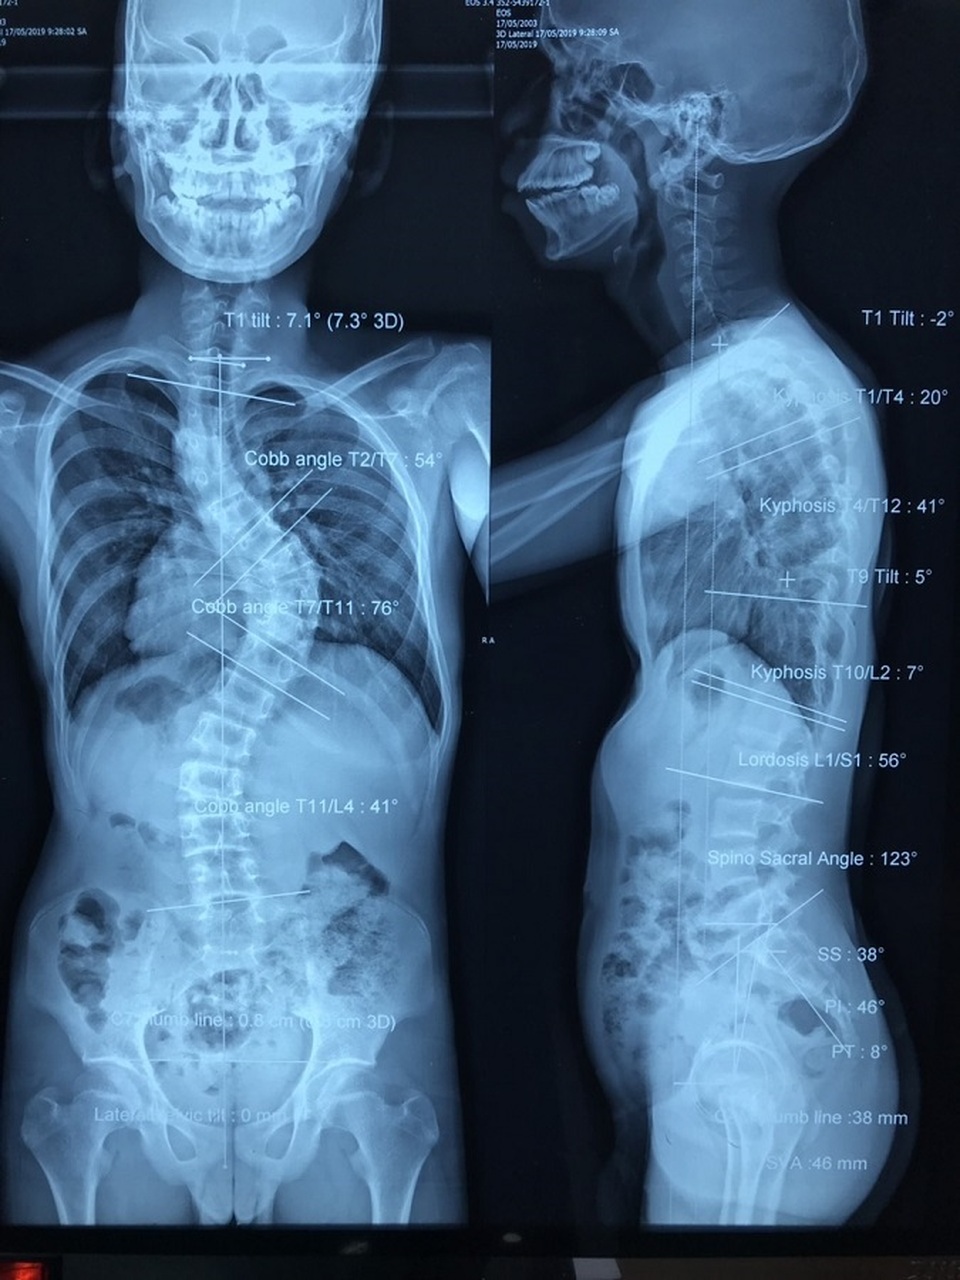

Cột sống của người bệnh cong vẹo như... xương rắn

TS.BS Trần Minh Trí, khoa Ngoại Thần kinh, Bệnh viện Chợ Rẫy cho biết: Nam bệnh nhân bị vẹo cột sống rất nặng, góc vẹo gù lên tới 76 độ gây biến dạng lồng ngực, xương ức bên trái lõm sâu, chèn ép tim phổi khiến bệnh nhân khó thở, nằm một chỗ cũng đau. Nếu không được can thiệp, bệnh nhân có thể đối mặt với nguy cơ yếu liệt, mất khả năng vận động do góc vẹo chèn ép tủy sống.